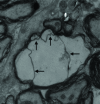

Myelinated nerves of mouse brain from the test group at 90 days post challenge. Rightward arrows indicate structures of myelin sheath between two nerve fibres which had become fuzzy and deformed, a leftward arrow indicates that there were some black depositions accumulated into larger particles, and a downward arrow indicates the detached invaginated myelin plasmalemma and vacuoles

The myelinated nerves of mouse brain from the test group at 97 days post challenge. The myelin had become curved and deposition or polymerisation of dispersed particles was obvious in the myelin sheath. Rightward arrows indicate that the cytoplasmic membrane was no longer integrated and leftward arrows indicate that stratification in the myelin sheath was more obvious where there were black pathogen-like particles accumulated